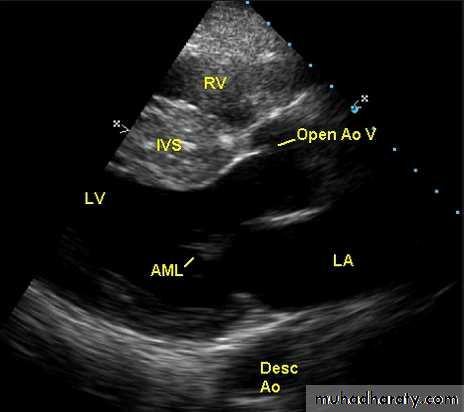

This is the most common form of cardiomyopathyGenetic disorder, usually with autosomal dominant transmission

• Hypertrophic cardiomyopathy

The hypertrophy may be generalised or confined largely to the interventricular septum (asymmetric septal hypertrophy or other regions (e.g. apical hypertrophic cardiomyopathy)

Pathophysiology

Dynamic LV outflow tract obstruction ( atleast >30 mm, usually > 50mm Hg)

Diastolic dysfunction

Myocardial ischemia

Mitral regurgitation

ECHO Echocardiography is diagnostic

Cardiovascular Diseases